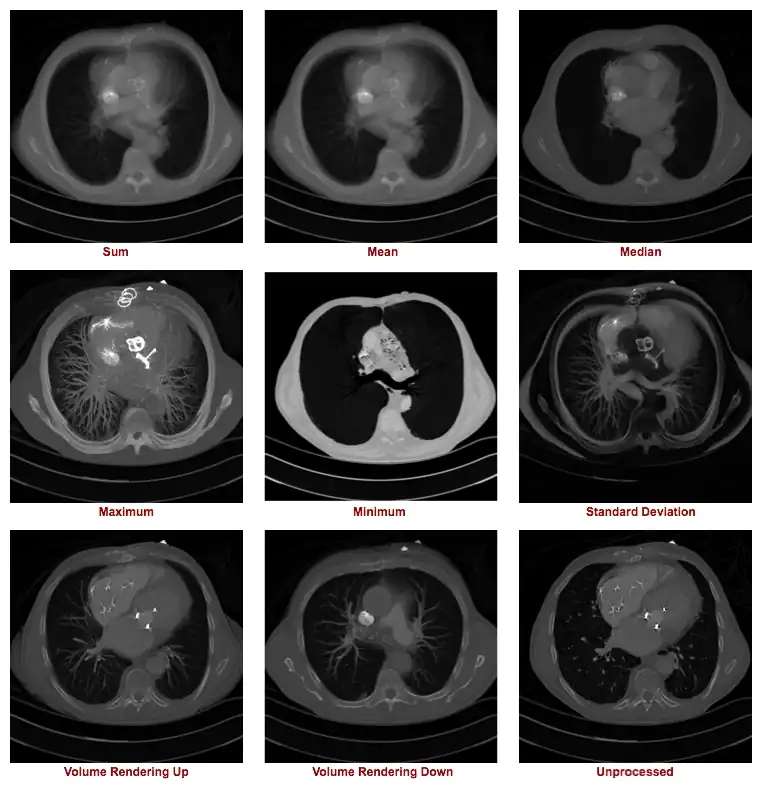

The figure below illustrates the outcome of a range of z-projection methods, with a single slice shown in the bottom right hand corner for reference purposes. The first image in the top left shows the result of summing 16 slices, and the other two images on that row show the results of computing the mean and median of these slices.

A range of z-projections of 16 axial slices from the CT scan, with a reference, single slice shown in the bottom right corner.

The first two images in the second row show the result of what are called a Maximum Intensity Projection (MIP) and a Minimum Intensity Projection (MinIP), respectively. A MIP evaluates each voxel along each line of voxels through the volume to determine the maximum voxel value and forms an image using the values so determined for each line. A MinIP uses the minimum voxel values, as illustrated in the following figure:

Notice that volume rendering can be applied from distal to proximal slices, as illustrated in our figure, as well as in the opposite direction, i.e. from proximal to distal slices. Hence the terms Volume Rendering Up and Volume Rendering Down used in our set of nine example images above.

The type of axial projection method appropriate to an individual patient study is dependent on the anatomical and/or functional information of relevance to the diagnostic process. Let's take the case of imaging contrast-filled blood vessels, for example, in our nine example images above. Note that a MIP can be used to give a visually-stunning impression of the vessel bed in the patient's lungs. There's little depth information in this projection, however, so that overlapping and underlying vessels can obscure lesions that might be present in blood vessels of interest. The application of this form of axial projection to angiography is therefore limited to studies where vessel overlap isn't an issue. The inclusion of voxel transparency and depth weighting in volume rendered images addresses this limitation of MIP processing.